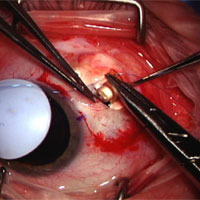

As a three resident-per-year program, one of the strongest aspects of ophthalmology training at Rush is the ability to learn comprehensive ophthalmology continuously for all three years. Residents follow their patients throughout their residency, developing a strong sense of continuity-of-care as a primary care doctor. State-of-the-art cataract extraction techniques are taught, including Femto-second laser assisted phaco, ORA aberrometer assisted surgery, and other modern image guidance technologies including the Callisto. The cataract surgery experience is quite busy, with most residents performing more than 200 procedures during their training. Residents benefit from having preoperative, operative, and postoperative contact with patients. The advantage of the rotational schedule, which allows continuity-of-care, ensures that patients who undergo surgery in the first or second year of training will be followed by the same resident for all three years. In general, routine procedures are performed during the first and second year, with more complicated operations and techniques being performed by the senior residents. Residents depart this program with the knowledge and expertise to be superb anterior segment surgeons. The Comprehensive Ophthalmology Section faculty who participate in the resident continuity clinic include Section Director Anjali S. Hawkins, MD, PhD, Thomas A. Deutsch, MD, Joseph B. Garber, MD, and Ronald S. Weiss, MD.